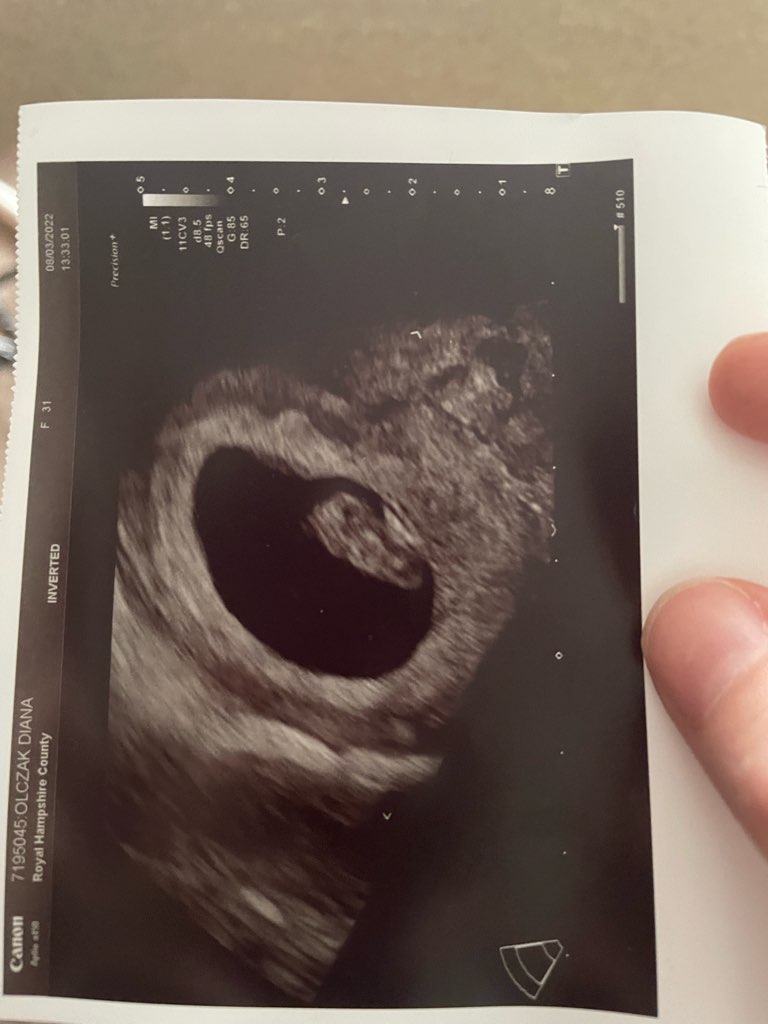

Ale ciąża żywa, 1.5cm fasolki z bijącym sercem.